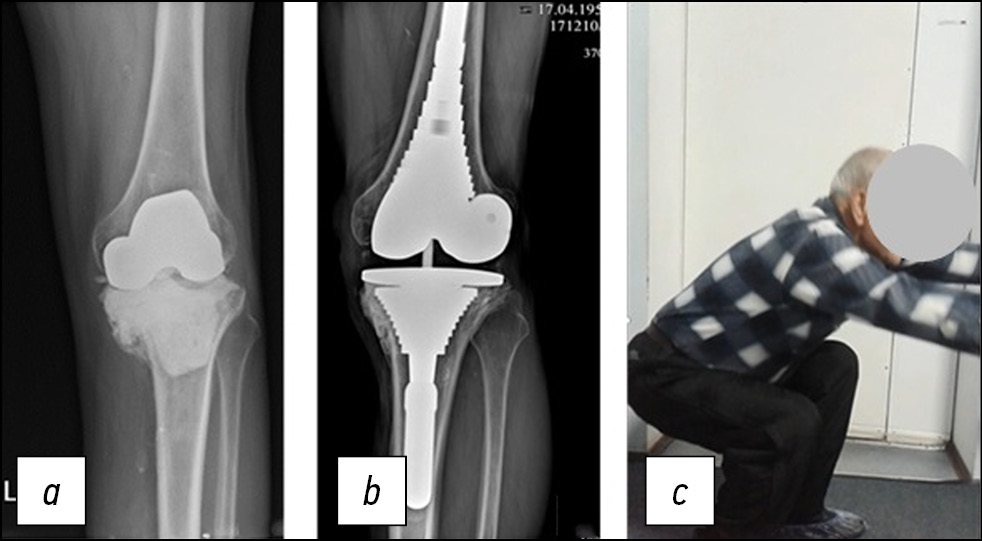

Пациент Е., 56 лет, поступил в НИИТОН для прохождения 2-го этапа лечения перипротезной инфекции с центральным дефектом типа F2А и периферическим промежуточным 5–10-миллиметровым дефектом медиального мыщелка большеберцовой кости T2А по AORI. Несмотря на значительный костный дефект большеберцовой кости, интраоперационно успешно достигнута первичная стабильная фиксация метафизарной втулки (рис. 3).

Согласно разработанному алгоритму, нами выбрана метафизарная фиксация посредством втулки с интрамедуллярным стержнем. На контрольных рентгенограммах через 9 лет после операции отмечены признаки остеоинтеграции (рис. 3, В) и отсутствие остеолиза. Также отмечена хорошая функция сустава (рис. 3, С).

Рис. 3. Рентгенограммы пациента Е., 56 лет, дефект типа F2А/T2A по AORI (a), контрольная рентгенограмма (b) и фото пациента (c) через 9 лет после установки ревизионной системы с метафизарной втулкой и стержнем.

Fig. 3. X-ray images of the 56 y.o. patient E. with AORI F2A/T2A defect (a). Control X-ray image (b) and the picture of the patient (c) taken 9 years after implanting a revision system with a metaphyseal sleeve and a shaft.